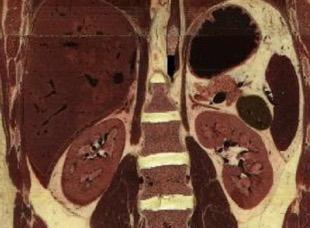

Área desnuda. El hígado en contacto directo con el tendón central del diafragma.

Contiene el hiato de VCI.

Comunica con el hiato esofágico y el espacio pararrenal anterior.

Colecciones “inflamatorias” abdominales llegan al tórax vía el hiato esofágico o por vía transdiafragmática